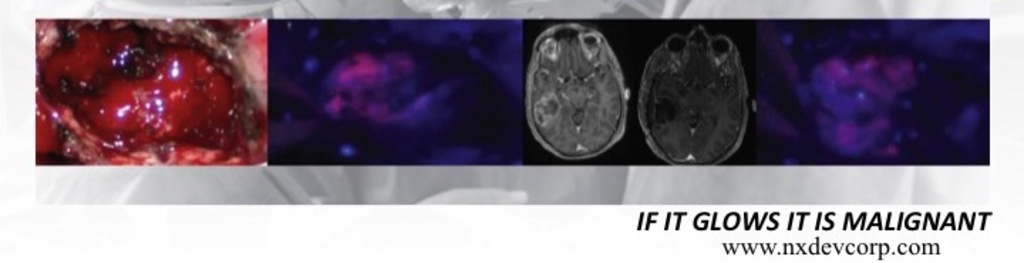

NXDC is developing Gliolan™ as an Orphan drug which enhances brain tumor visualization improving tumor removal and outcomes. https://vimeo.com/122150642

NXDC has exclusive US rights for Gliolan™ (5-aminolevulinic acid), which is approved ex-US with 58,000 patients treated. Gliolan™ is in high demand and is expected to be available in 2016 through an FDA program at leading US brain tumor centers. Gliolan™ improves tumor resection aligning strategic interests with blockbuster glioblastoma therapies. Funds on hand enable FDA approval (in 2016); a new $3M accelerates Gliolan’s market penetration